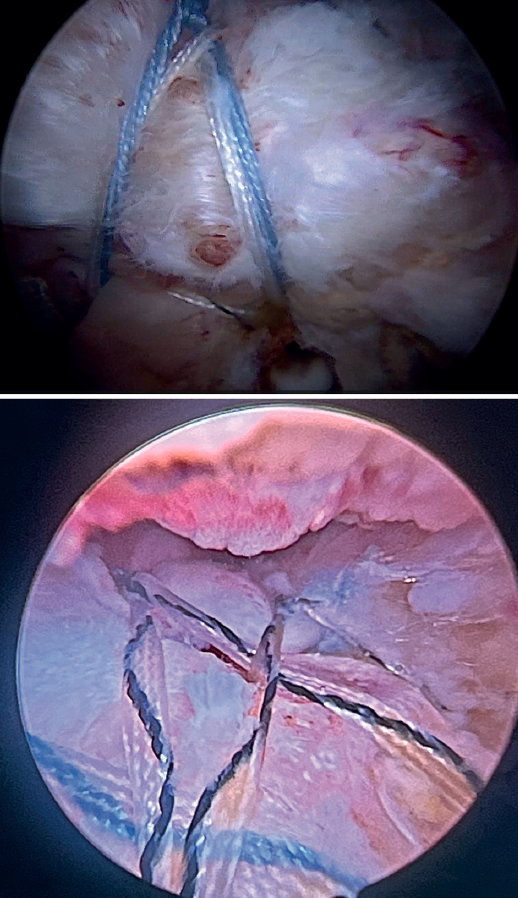

Using penetrating forceps through the anterior portal, the surgeon penetrates the LPB and retrieves one of the suture threads, performing a self-locking Lasso suture in the same step. This is done with two of the three anchoring threads to ensure a correct LPB grip to the footprint of the greater tuberosity and that the tendon does not fray; we do not cut the two threads after knotting (Figures 4, 5 and 6). We also consider it very important to apply the biceps tendon, keeping it as flat and anatomical as possible, avoiding twisting or excessive distension of the tendon. Subsequently, a tenotomy of the LPB distal to these sutures is performed (Figure 7), thus allowing the LPB to function as a superior capsular reconstruction, restricting the ascent of the humeral head.

Tension-free repair of the supraspinatus tendon is then made, using the free thread left at the anchoring and taking advantage of the two sutures passed through and knotted to the proximal LPB fragment (Figures 8, 9 and 10).